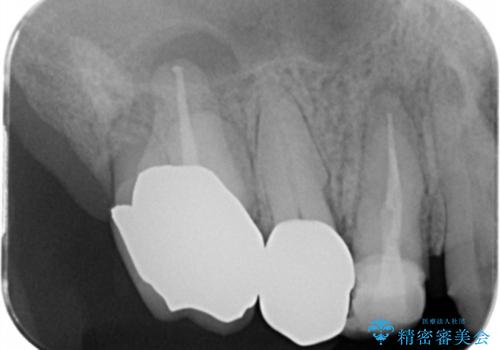

咬合の崩壊 金属床義歯で咬合機能の回復

- 「体調が悪く歯医者に行けない間にどんどん歯が悪くなってしまった、治療をしたい。」と咬合機能の回復を希望され来院されました。

「大規模な手術は避けたい。」と言う希望を鑑み、インプラントではなく残せる歯の連結セラミッククラウンの作製、金属床義歯を用いてしっかりと咬合機能を回復できるよう治療を進めます。

年齢と体調を考慮して、インプラントではなく入れ歯で咬合機能の回復を達成する治療計画としました。